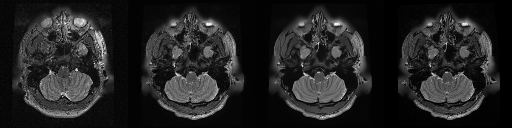

HCP T2w dataset

We utilize images from the publicly available Human Connectome Project (HCP) [51] T2-weighted (T2w) images dataset for the task of compressed sensing, which contains brain images from 47 patients. The HCP dataset includes cross-sectional images of the brain taken at different levels and angles.

Compressed sensing

We train a flow-based model from scratch on 10,000 randomly sampled images, utilizing the ncsnpp architecture [9] with minor adaptations for grayscale images. We employ compression rates , meaning . The measurement operator is given by a subsampled Fourier matrix, whose sign patterns are randomly selected. We evaluate our reconstruction algorithm’s performance on 200 randomly sampled test images.

We present the quantitative and qualitative results of compressed sensing in Tab. 1 and Fig. 4, respectively. As shown in Tab. 1, our method consistently achieves the best performance across varying compression rates . In Fig. 4, our method produces reconstructions that are more faithful to the original images, with fewer artifacts, leading to higher accuracy and clearer details.